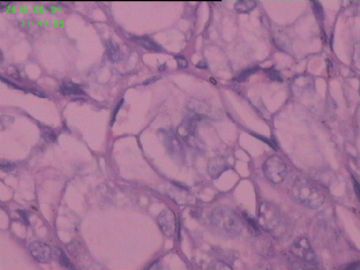

灰白结节2枚,其一2.5x1.8x1.5cm,包膜完整,内为褐色胶质,其二3x2.5x1.5cm包膜完整,切面灰白实性。附件镜下为后者。

可能楼主看到那些核的变化吧?但是没有其他支持的条件,还是应该是结甲。

就这几幅图似乎不够说明问题,细胞有一定的异型性,但是,最好能采到交界处的情况再判断。癌与非癌,最好能有组织结构与细胞异型性结合来看。

有些核透明,无其它特点,恶性证据是没有。